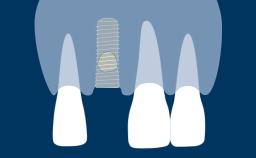

As implant dentistry has evolved, the esthetic outcome of implant therapy has gained increasing importance. As a result both patients and those in the dental profession have become increasingly interested in the attractive esthetic characteristics of all-ceramic prostheses. Extensive research is being devoted to developing, testing, and reviewing the characteristics and performance of ceramic materials in connection with implant therapy. Nevertheless each patient is unique, and it is important to ensure that the appropriate prosthodontic material is selected for each case. This step often requires a team approach in which both the prosthodontic dentist and the dental technician are involved. This module will discuss the different parameters that should influence the decision-making process for selection and use of ceramic materials in implant prostheses.

- describe prosthodontic indications for ceramic materials in implant prostheses and abutments